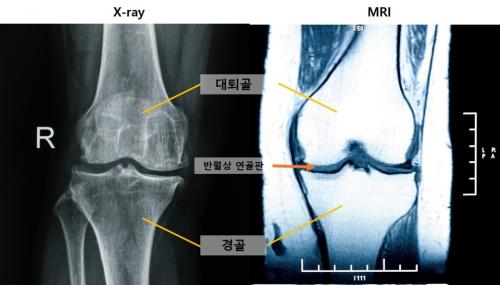

- ¿¢½º·¹ÀÌ ¹× MRI ¹«¸ »çÁø(Ãâó: °ÔƼÀ̹ÌÁö¹ðÅ©, Á¦°ø: ¼¿ï´ëº´¿ø)

[ÇコÄÚ¸®¾Æ´º½º / ¹Ú¿øÁø] ¹«¸ °üÀý¿°À» Á¶±â¿¡ ¹ß°ßÇÒ ¼ö ÀÖ´Â »õ·Î¿î Áø´Ü ÁöÇ¥°¡ È®ÀεƴÙ. ¿¢½º·¹ÀÌ¿¡¼ Á¤»óÀ¸·Î Áø´ÜµÈ ¹«¸À̶óµµ, MRI¿¡¼ ‘Áß¾Ó ´ëÅð°ñ ¿¬°ñ ¼Õ»ó’ ¼Ò°ßÀÌ °üÂûµÈ´Ù¸é ¹«¸ °üÀý¿°ÀÌ ÀÌ¹Ì ÁøÇàµÇ°í ÀÖÀ» °¡´É¼ºÀÌ ³ô´Ù´Â »ç½ÇÀ» ±¹³» ¿¬±¸ÆÀÀÌ ±Ô¸íÇß´Ù. ¶Ç MRI·Î ‘³»Ãø ¹Ý¿ù»ó ¿¬°ñ µ¹Ãâ’ÀÌ °üÂûµÇ¸é °üÀý¿°ÀÌ ½É°¢ÇØÁú À§ÇèÀÌ ³ôÀº °ÍÀ¸·Î ³ªÅ¸³µ´Ù.

¹«¸ °üÀý¿° Ãʱ⿡´Â ¿¬ºÎÁ¶Á÷(¿¬°ñ, ¹Ý¿ù»ó ¿¬°ñÆÇ µî)¿¡¼ ¸ÕÀú º¯È°¡ ¹ß»ýÇÏÁö¸¸, ÀϹÝÀûÀ¸·Î Áø´Ü¿¡ Ȱ¿ëµÇ´Â ¿¢½º·¹À̷δ ÀÌ·± º¯È¸¦ ÀÏÂï ÆÄ¾ÇÇÏ´Â µ¥ ÇѰ谡 ÀÖ´Ù. ¿¬ºÎÁ¶Á÷À» °üÂûÇϱ⠿ëÀÌÇÑ MRI´Â Á¢±Ù¼ºÀÌ ¶³¾îÁö¸ç, ÀÌó·³ ¼·Î ´Ù¸¥ Ư¼ºÀ» °¡Áø µÎ °Ë»ç ¹æ¹ýÀÇ ¿¬°ü¼ºÀ» Àå±âÀûÀ¸·Î ºÐ¼®ÇÑ ¿¬±¸´Â µå¹°¾ú´Ù.

±× °á°ú, °üÀý¿° ÁøÇà ½Ã °¡Àå ¸ÕÀú ³ªÅ¸³ª´Â º¯È´Â ‘Áß¾Ó ´ëÅð°ñ ¿¬°ñ ¼Õ»ó’À̾ú´Ù. ÀÌ ¼Õ»óÀº ¿¢½º·¹ÀÌ¿¡¼ Á¤»óÀ¸·Î ¿©°ÜÁö´Â °üÀý¿° 0±âºÎÅÍ °üÂûµÇ¾î, MRI°¡ ¹«¸ °üÀý¿° Ãʱ⠺¯È¸¦ È®ÀÎÇÏ´Â µ¥ Áß¿äÇÑ µµ±¸ÀÓÀ» º¸¿©Áá´Ù.

°üÀý¿° ÁøÇà À§ÇèÀÇ °¡Àå °·ÂÇÑ ¿¹Ãø ÀÎÀÚ´Â ‘¹Ý¿ù»ó ¿¬°ñ Å»Ãâ’À̾ú´Ù. ÃßÀû °üÂû ½Ã°£Àº À¯ÀǹÌÇÑ ¿¬°ü¼ºÀÌ ¾ø¾î, ½Ã°£ °æ°úº¸´Ù´Â ¹«¸ÀÇ ±¸Á¶Àû º¯È°¡ °üÀý¿° ÁøÇàÀ» ÁÖ·Î À¯µµÇÏ´Â °ÍÀ¸·Î È®ÀεƴÙ. °üÀý¿° ÁøÇà¿¡ µû¶ó MRI»ó ¹«¸ Áß¾Ó¿¡¼´Â ¿¬°ñ·¹Ý¿ù»ó ¿¬°ñÆÇ·»À, ÈĹ濡¼´Â ¹Ý¿ù»ó ¿¬°ñÆÇ·¿¬°ñ·»À ¼ø¼·Î ¼Õ»ó ¾ç»ó¿¡ Â÷À̰¡ ÀÖ¾ú´Ù.

- ¹«¸ °üÀý¿° ÁøÇà¿¡ µû¸¥ MRI ¼Ò°ß

¿¬±¸ÆÀÀº Ãß°¡ÀûÀ¸·Î °üÀý¿° Ãʱâ MRI ¼Ò°ß(Áß¾Ó ´ëÅð°ñ ¿¬°ñ ¼Õ»ó)°ú ¿¬°üµÈ ¿¢½º·¹ÀÌ ÁöÇ¥¸¦ ºÐ¼®Çß´Ù. ±× °á°ú, °æ°ñ °ñ±Ø, ³»Ãø °üÀý° ÇùÂø, ´ëÅð°ñ °ñ±Ø ¼ø¼·Î ¿¢½º·¹ÀÌ ¼Ò°ßÀÌ ³ªÅ¸³µ°í, À̵éÀº ¸ðµÎ ¿¬°ñ ¼Õ»ó°ú ¿¬°ü¼ºÀÌ ÀÖ¾ú´Ù.